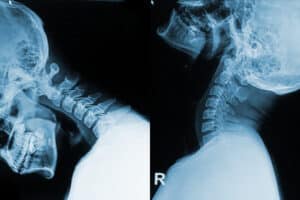

Whiplash associated disorders and ligament damage

Marc Darrow, MD, JD. In the more than 27 years we have been helping patients with their chronic pain, we have seen many people with hyper-extended neck injuries, or, in simpler terms whiplash injury. We have also seen patients who suffered from long-term effects of their whiplash injury until such time as they were diagnosed … Continue reading Whiplash associated disorders and ligament damage